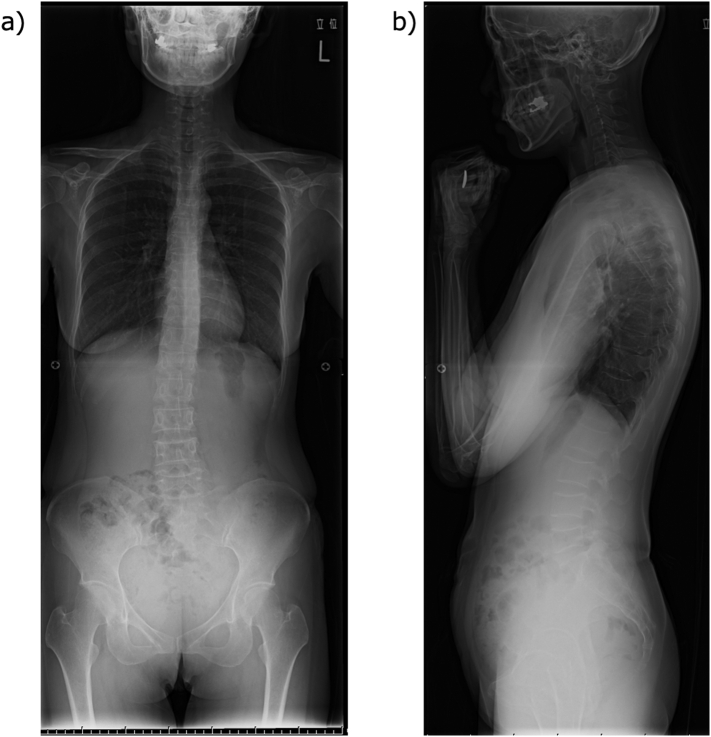

Fig. 1.

Simple X-ray of the whole spine

a) Frontal, b) Lateral

A wedge-shaped deformity is observed in the 5th, 7th, 8th, 9th, and 10th thoracic vertebrae and the 4th and 5th lumbar vertebrae.

A simple X-ray showed multiple vertebral body deformities (Fig. 1). Magnetic resonance imaging (MRI) showed T1 low and T2 high signals in the 4th, 5th, 7th, 8th, and 9th thoracic vertebrae and the 1st, 4th, and 5th lumbar vertebrae, indicating fresh multi-vertebral fractures (Fig. 2). Bone mineral density was assessed using dual X-ray absorptiometry (DXA) (Discovery DXA System; Hologic Inc., Marlborough, MA, USA). It was 0.498 g/cm2 (49 % young adult mean [YAM]) for the lumbar spine and 0.498 g/cm2 (63 % YAM) for the hip (Table 1).